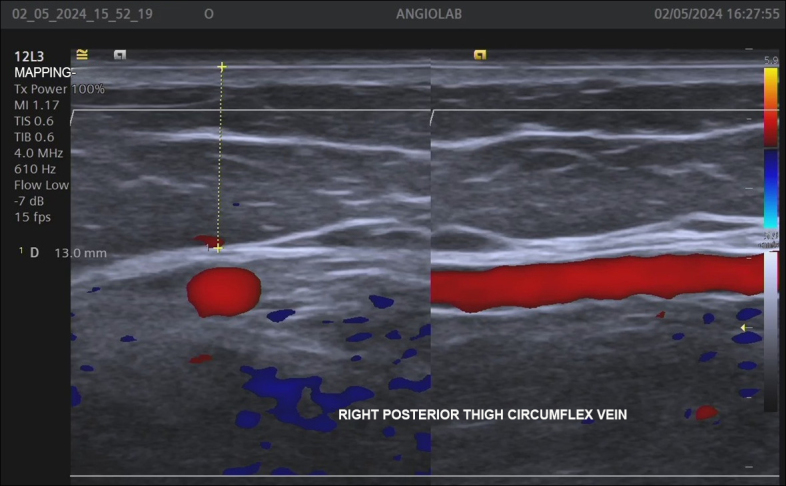

Background: The Giacomini vein (GV) can transfer reflux from perineal veins, tributary veins, and perforators of the thigh to the small saphenous vein (SSV). Vascular ultrasound with Doppler (VUD) is the preferred method for detecting reflux in specific veins such as the GV.

Objective: To identify GV depth and diameter, reflux in the GV, and presence of reflux in the SSV caused by the GV.

Methods: A cross-sectional, retrospective study was conducted in women undergoing lower limb venous mapping for varicose vein surgery. The following parameters were analyzed in GVs in which reflux was detected: segmental or diffuse reflux pattern; GV diameter and depth; and reflux in the SSV caused by the GV.

Results: 340 of the 2368 women evaluated were included in the study because they had a GV, totaling 511 veins analyzed, 150 (29.4%) of which had reflux. The diameters of the 150 GVs with reflux ranged from 1.5 to 7.8 mm and their depth varied from 4 to 25 mm. Most GVs with reflux (91.3%) had a segmental reflux pattern. The majority (66%) of refluxing GVs drained reflux into the popliteal vein through the saphenopopliteal junction, while reflux was transferred to the SSV in 34 veins (22.7%), and was drained by a tributary vein in the thigh in 15 veins (11.3%).

Conclusions: Approximately one-third of the studied GVs had reflux, mostly segmental, mean caliber was 2.7 mm, and mean depth was 11 mm. Reflux in the SSV originating from the GV was detected in 22% of the evaluated veins.